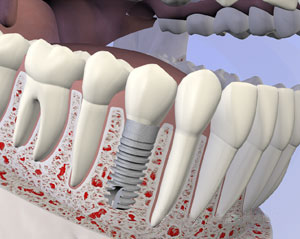

What are Dental Implants?

Dental implants are biocompatible screws or posts placed in the jawbone to replace the roots of missing teeth and support dental restorations such as a crown or implant denture. Most dental implants are made of titanium, the same material used for joint replacements. However, ceramic or zirconia implants are sometimes used.

The tooth implant is surgically placed in the jawbone, where it gradually fuses with the surrounding bone through osseointegration. Once the implant is fused and stable, an abutment (a slender pin or clasp) is used to attach it to a dental crown or restoration permanently.

What is the Dental Implant Process?

Placing a single dental implant takes 30 to 60 minutes, and for multiple implants, the process takes anywhere from one to three hours. Before surgery, we may prescribe antibiotics and oral conscious sedation or nitrous oxide (laughing gas) to relax you during implant surgery. The local area is numbed with an anesthetic. Your surgeon will discuss these options with you at your initial consultation.

The dentist makes a small incision in your gums, revealing the bone, and gently inserts the implant into the empty tooth socket. During healing, the top of the implant may be covered by gum tissue or exposed, depending on the surgeon’s judgment and the type of restoration that will be used.

1. Normal

2. Tooth Loss

3. Healed Bone

4. Implant Placed

5. Healing

6. Implant Restored